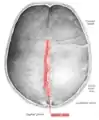

La suture sagittale

Vue interne de la suture sagittale.

La suture sagittale (ou suture bipariétale ou suture interpariétale ou suture pariétale ou suture rhabdoïde) est la suture crânienne qui relie les bords supérieur des deux os pariétaux.

Elle présente deux repères anatomiques : le bregma formé par son intersection avec la suture coronale, et le vertex du crâne.